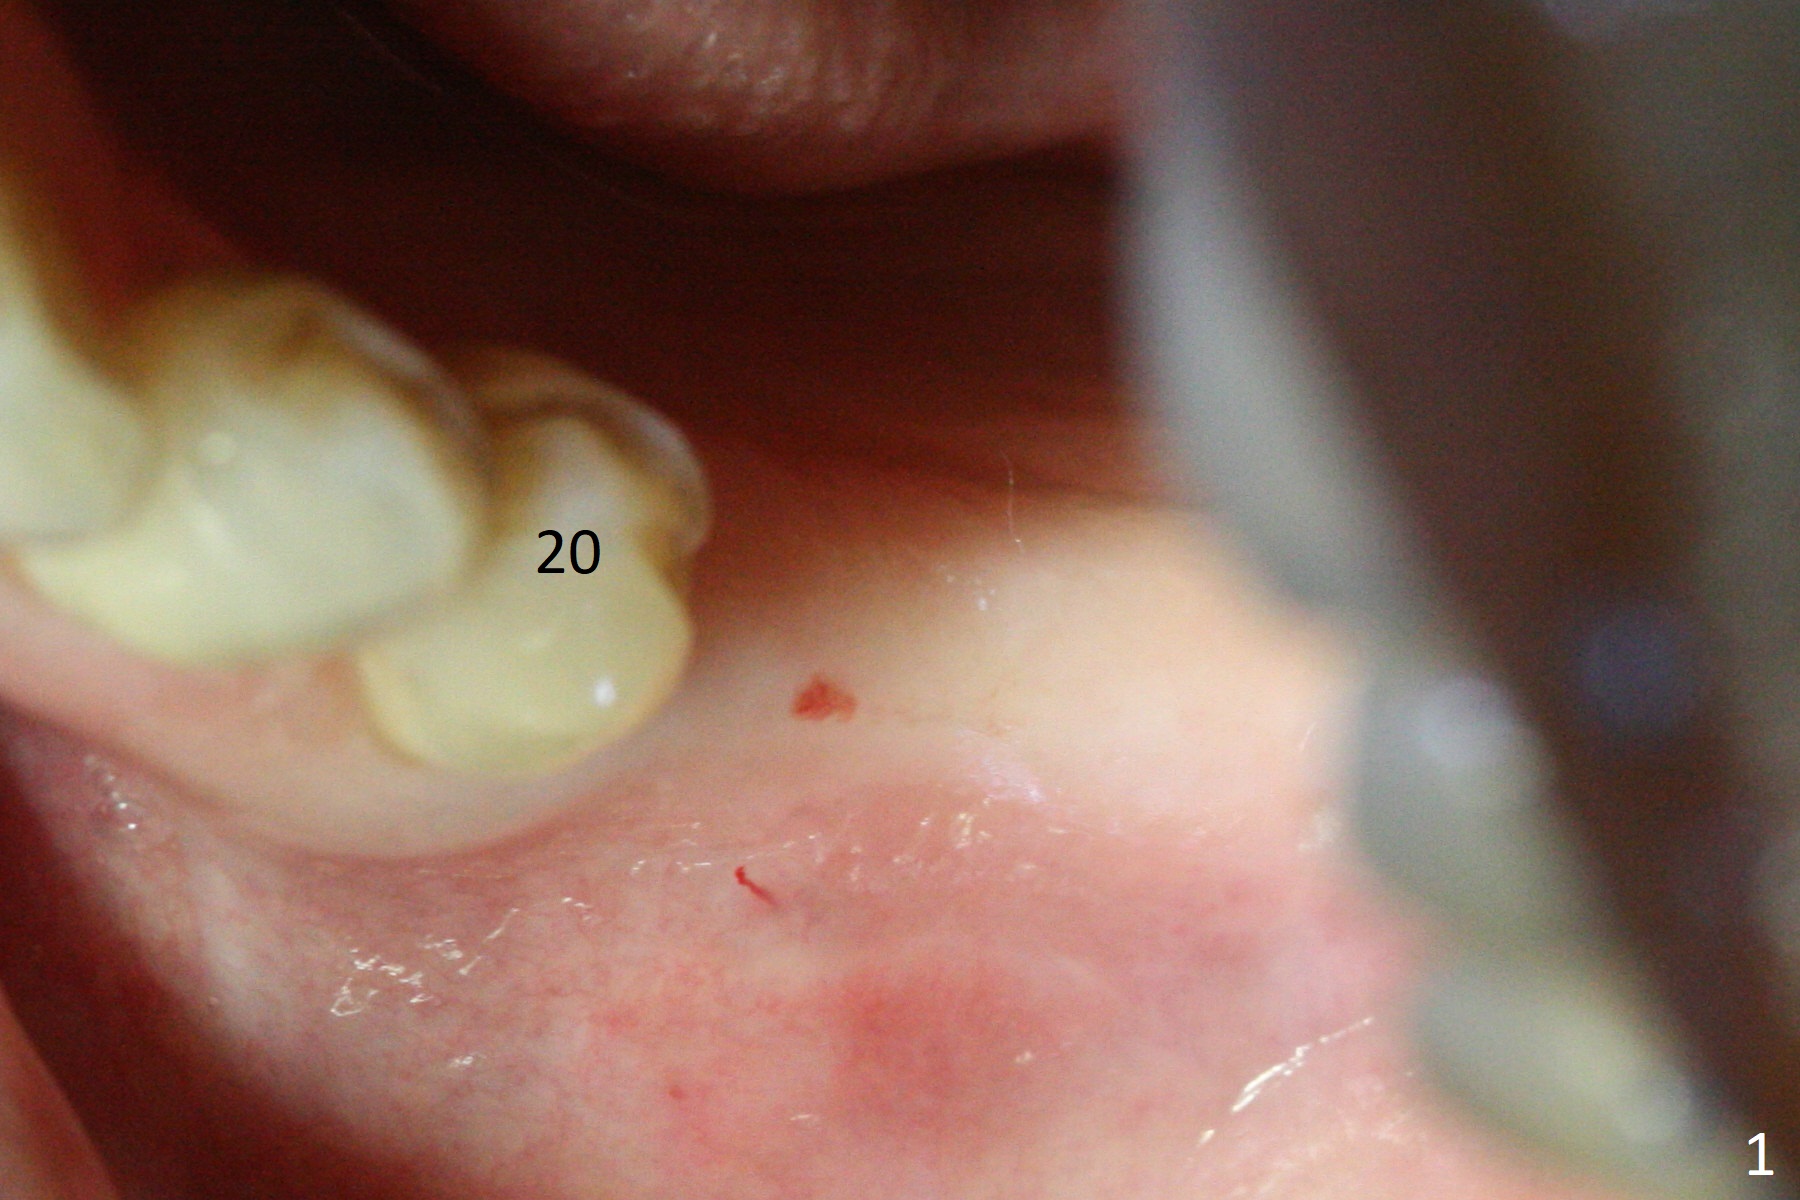

After incision over the narrow ridge at #30 (Fig.1) and ridge reduction (Fig.2 black area on the top; Fig.4 arrowheads), a 1.6 mm drill is used (Fig.2 (CBCT coronal section) long vertical black area) to start BEB (bone expansion and Bending). It is expected that the cortical and cancellous bone of the buccal (B) and lingual (L) plates can be expanded after use of Magic Expanders (ME) and 1.6 mm drill alternatively. In fact it appears that only the cancellous bone is pushed after MEs from 3 to 4.3 mm (Fig.3 arrows). There is no apparent cortical bone bending. There may be cancellous bone condensation. Dummy (Fig.4) and definitive (Fig.5) implants (4x11 mm) are placed. Since torque is 20 Ncm, a 5.5x4 mm healing abutment is placed (Fig.5,6 H). The opposing tooth is supraerupted; intrusion is pending. A 6x4(2) mm abutment is placed with a provisional 2 months postop. There is enough occlusal clearance. Impression is taken 5 months postop with difficulty because of subgingival margin (Fig.7). After cementation, the patient feels discomofort, which is relieved when the mesial embrasure is enlarged. Return to Lower Molar Immediate Implant, Armaments Xin Wei, DDS, PhD, MS 1st edition 12/14/2017, last revision 09/16/2018